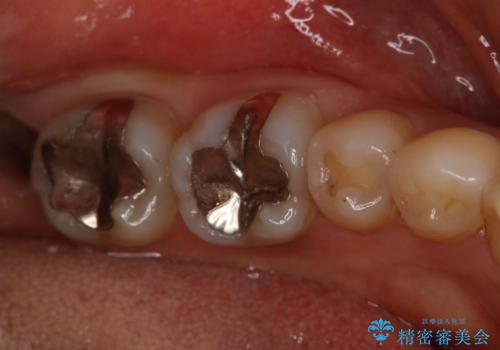

下の奥歯の銀歯を白くしたい

- 左下奥歯のメタルインレーを白くしたいと希望された患者様です。

形態、切削量などを考慮し、セラミックインレーにて治療を行いました。

メタルインレー、う蝕除去後にCRにて裏層した上で、形成・印象を行いました。